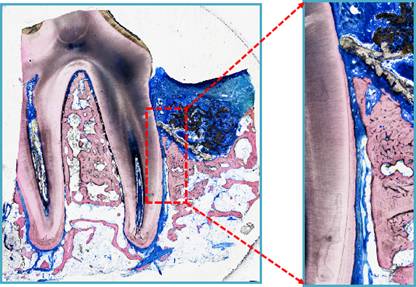

特等奖作品《扎根》